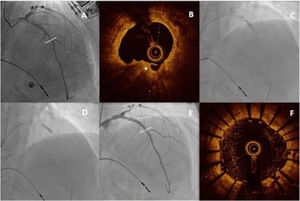

Desarrollo de técnicas y dispositivos diseñados para el tratamiento de lesiones gravemente calcificadasLa presencia de una calcificación grave se asocia a peores resultados inmediatos del ICP (menor expansión del stent y más disecciones) y peor evolución clínica posterior (más reestenosis y trombosis del stent). En la actualidad, a la aterectomía rotacional se le han sumado otros dispositivos, como la litotricia intracoronaria, el láser coronario y la aterectomía orbitacional, que están permitiendo obtener unos excelentes resultados en este contexto anatómico, tanto de forma aislada41 como combinando varias técnicas42,43 (fig. 4).

Caso realizado en el Hospital Universitario La Paz sobre una lesión gravemente calcificada en el segmento proximal de la arteria descendente anterior (A). Tras realizar aterectomía rotacional (B), al no dilatarse con éxito mediante un balón no compliante (C), se realizó litoplastia intracoronaria (D) y se implantaron dos SFA con excelente resultado tanto mediante angiografía (E) como mediante tomografía de coherencia óptica (F)43.